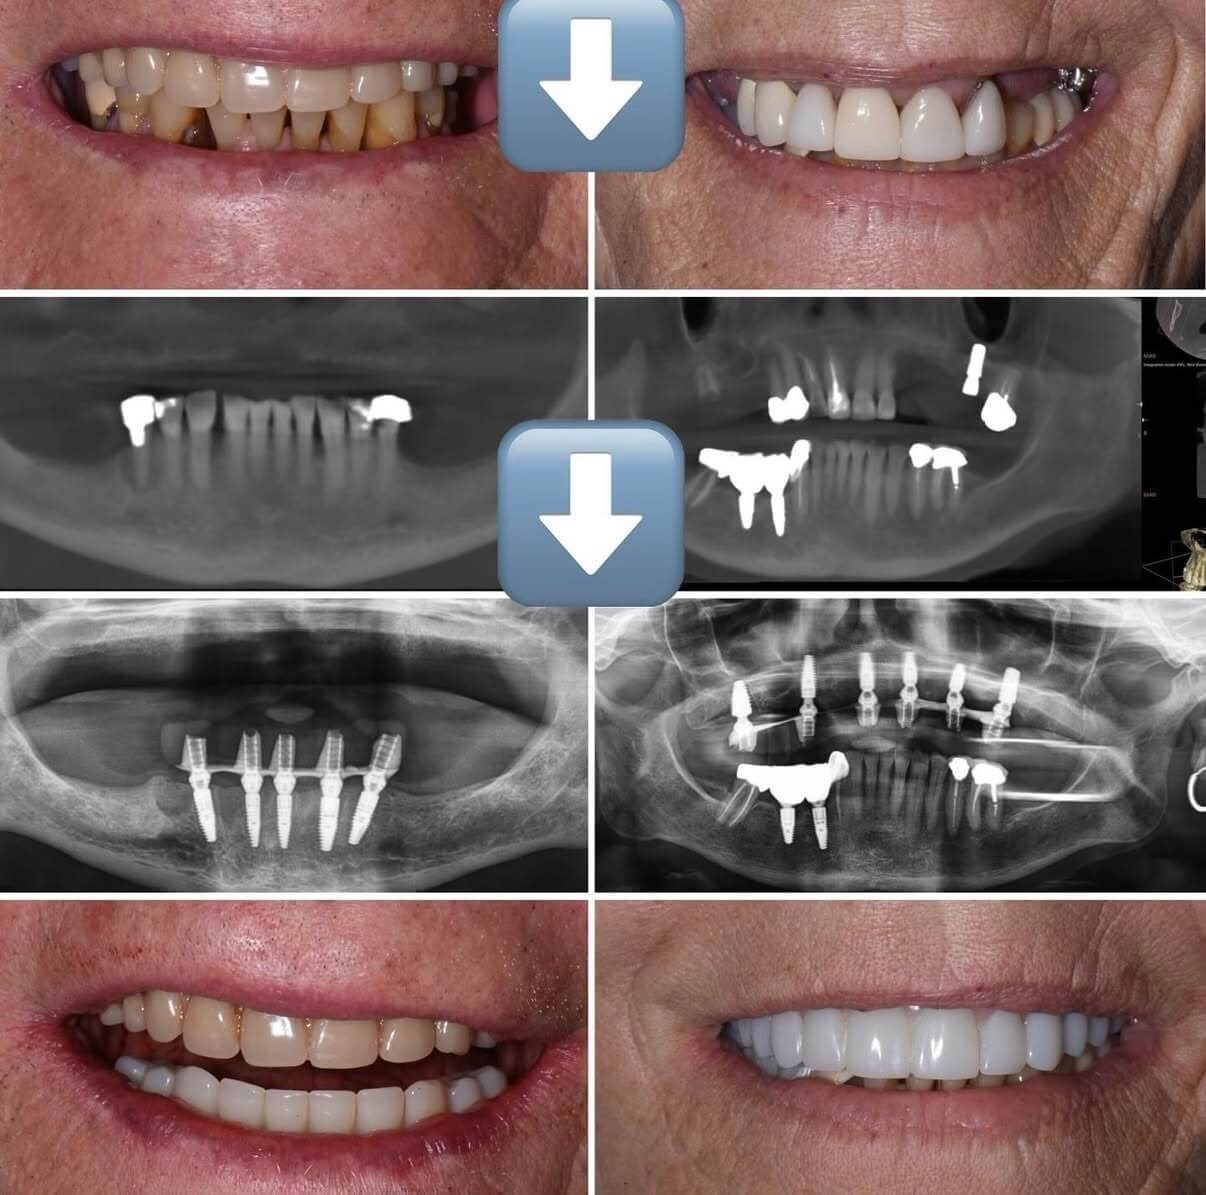

If you are struggling with missing teeth, loose dentures, or teeth that can no longer be saved, hybrid restorations may be the life-changing solution you’ve been looking for.

Hybrid restorations provide a secure, fixed full-arch restoration that looks, feels, and functions like natural teeth — without the inconvenience of removable dentures.

Hybrid restorations are a full-arch tooth replacement solution that combines dental implants with a custom, fixed prosthetic bridge. The prosthesis is securely attached to implants placed in the jaw, meaning it does not come out like traditional dentures.

Full-Arch Hybrid Restorations

• Replaces an entire upper or lower arch

• Typically supported by 4–6 implants

• Fixed, non-removable teeth

• Restores chewing function and confidence